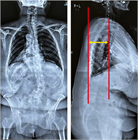

1. 若年者での脊柱変形は、先天性側弯症や思春期に発症する特発性側弯症が多く、通常痛みや機能障害を伴わない場合が多いが、成長に伴い変形が増悪する可能性が高いので見過ごしてはならない。特に特発性側弯症は、思春期の急速な成長期に進行するリスクが高いため、早期発見と適切な介入が重要である。